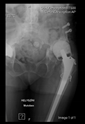

The guiding wire was inserted and controlled with fluoroscopy flashes (Figure 4). The drilling and reaming were carried out in accordance with the recommendations:

Figure 4.

The biocompatible aiming device after insertion of the guiding wire.

In all the cases operated with the above-described targeting procedure, the stems of the cups remained between the cortical bone surfaces without perforation of the linea terminalis, as shown by postoperative radiographs. There were no complicated surgical situations. In 16 cases, the wound healings were uneventful, and the hips were able to bear weight again after postoperative rehabilitation.